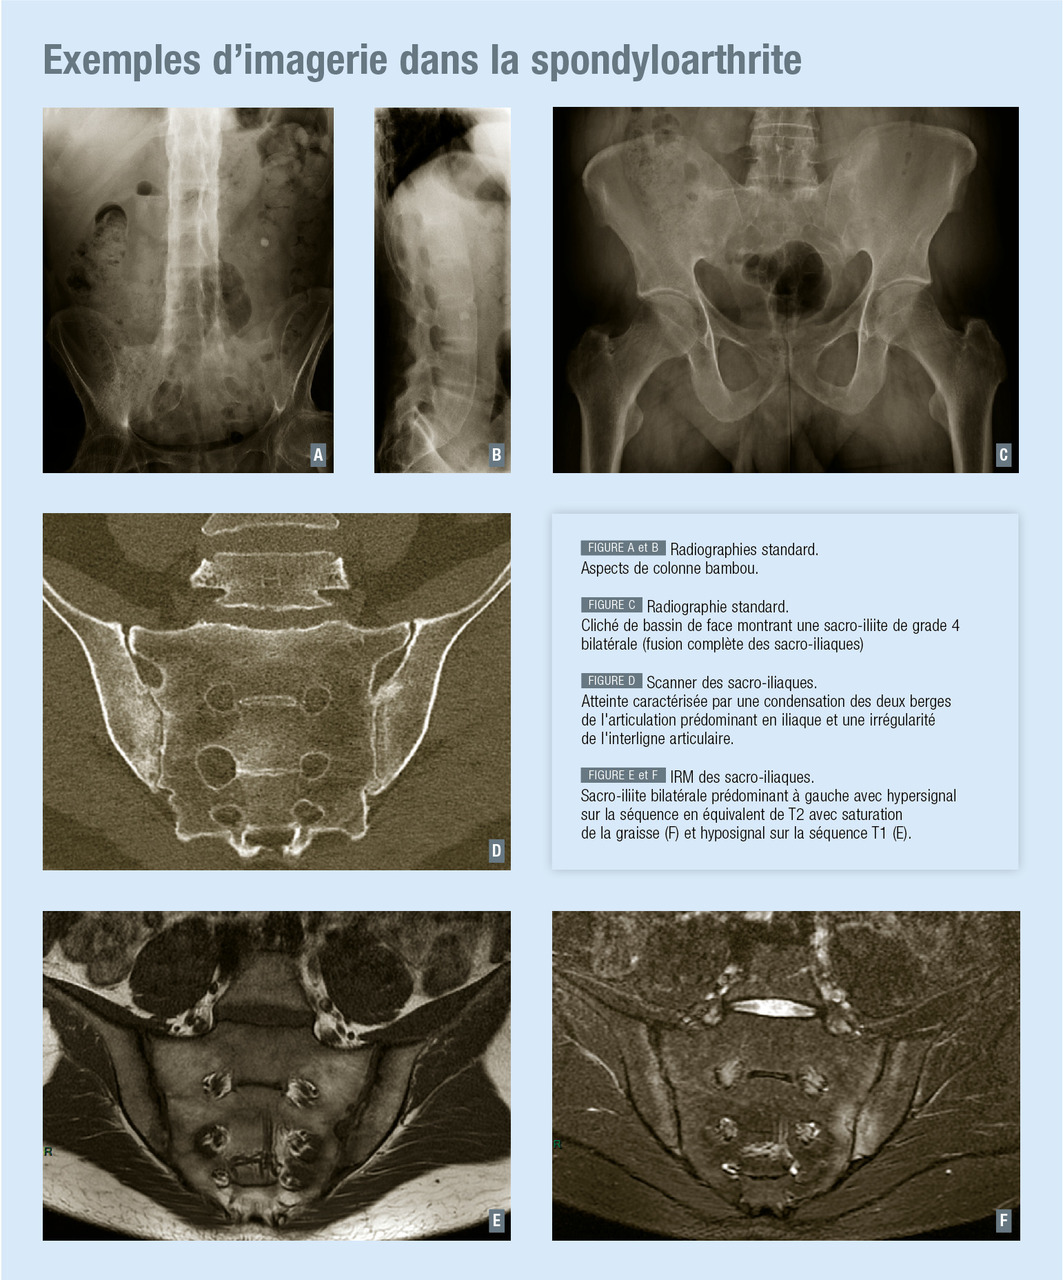

Radiologie conventionnelle : elle est largement utilisée du fait de son accès facile, de son coût modéré et de la faible irradiation qu’elle induit. Toutefois, la plupart des modifications structurales n’apparaissent qu’après plusieurs années d’évolution. La radiographie standard ne permet donc pas un diagnostic précoce de spondyloarthrite.

Le bilan minimal doit comporter une radiographie du bassin de face, des clichés du rachis cervical, thoracique et lombaire de face et de profil. En fonction des manifestations cliniques, d’autres clichés peuvent être demandés.

Les différentes anomalies à rechercher correspondent à l’atteinte enthésitique qui débute par une érosion de l’os sous-chondral à l’insertion de l’enthèse, dont l’évolution se fait vers une densification de l’os pour finalement aboutir à la formation d’une excroissance osseuse ou enthésophyte.

De façon plus spécifique, on décrit en fonction du site étudié :

la radiographie du bassin : l’atteinte radiologique des sacro- iliaques est gradée entre 0 (normal) et 4 (ankylose osseuse complète), les grades intermédiaires combinant de façon variable érosions et ossifications. Le grade 1 correspond à des anomalies débutantes encore douteuses, le grade 2 à des anomalies plus franches, le grade 3 à des anomalies certaines ;

les radiographies du rachis : aspect initial de mise au carré de la vertèbre (érosion de l’angle antérieur), puis d’ostéite de Romanus (condensation osseuse du coin vertébral antérieur), puis de pont osseux intervertébral que l’on appelle syndesmophyte lorsqu’il est complet et est responsable de l’aspect de colonne bambou lorsqu’il s’associe à une ossifications médiane du liga­ments inter-épineux (image en triple rail sur un cliché de face).

Scanner des sacro-iliaques : dans certains cas où la radiographie standard est douteuse, elle peut être complétée par un scanner des sacro-iliaques qui visualise mieux les lésions élémentaires, notamment les érosions. Cependant, le caractère irradiant de l’examen limite son utilisation chez des patients souvent jeunes en âge de procréer et il n’est donc pas réalisé en première intention.

Imagerie par résonance magnétique (IRM) : elle peut mettre en évidence des anomalies inflammatoires précoces, souvent bien avant que n’apparaissent des lésions structurales visibles sur les radiographies. Cette particularité en fait aujourd’hui l’un des outils privilégiés pour le diagnostic précoce de la spondyloarthrite.

On y recherche des anomalies de signal de type inflammatoire (hyposignal T1, hypersignal T2 après suppression du signal de la graisse, rehaussement du signal après injection de gadolinium) principalement de part et d’autre des articulations sacro-iliaques, mais pouvant intéresser également les coins vertébraux ou les plateaux vertébraux.